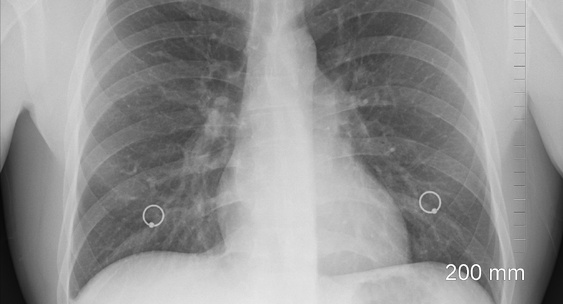

Анализ продемонстрировал, что у людей с критично низким уровнем витамина D в крови (менее 15 нмоль/л) риски госпитализации по поводу респираторных инфекций оказались на 33% выше, чем у имевших показатели 75 нмоль/л и выше.Planet Today

Исследование проводилось на основе медицинских данных 36 тысяч участников из базы UK Biobank.RuNews